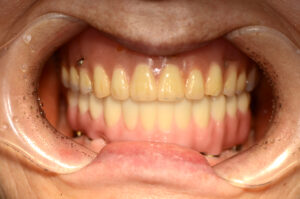

위에 완성된 사진을 보시면 전체 임플란트가 완성이 된 모습을 볼 수 있는데 환자분은 악궁이 작아 14개의 치아가 아닌 12개의 치아 기능을 회복하였어요.

환자 개인마다 구강의 크기, 잇몸뼈의 상태 모두 다르기 때문에 보철물을 제작할 때 여러 사항을 고려하여 제작이 이루어져야 해요.

풀아치임플란트가 완료된 후의 사진을 보시게 되면 상악 치아들과도 올바른 교합이 이루어지고 있는 것을 볼 수 있으며 고정된 치아들에 대해 큰 만족감을 느끼셨어요. 심미적으로도 만족해하셨으며 추후 상악에도 풀아치임플란트를 고려해 보시겠다고 하셨어요.